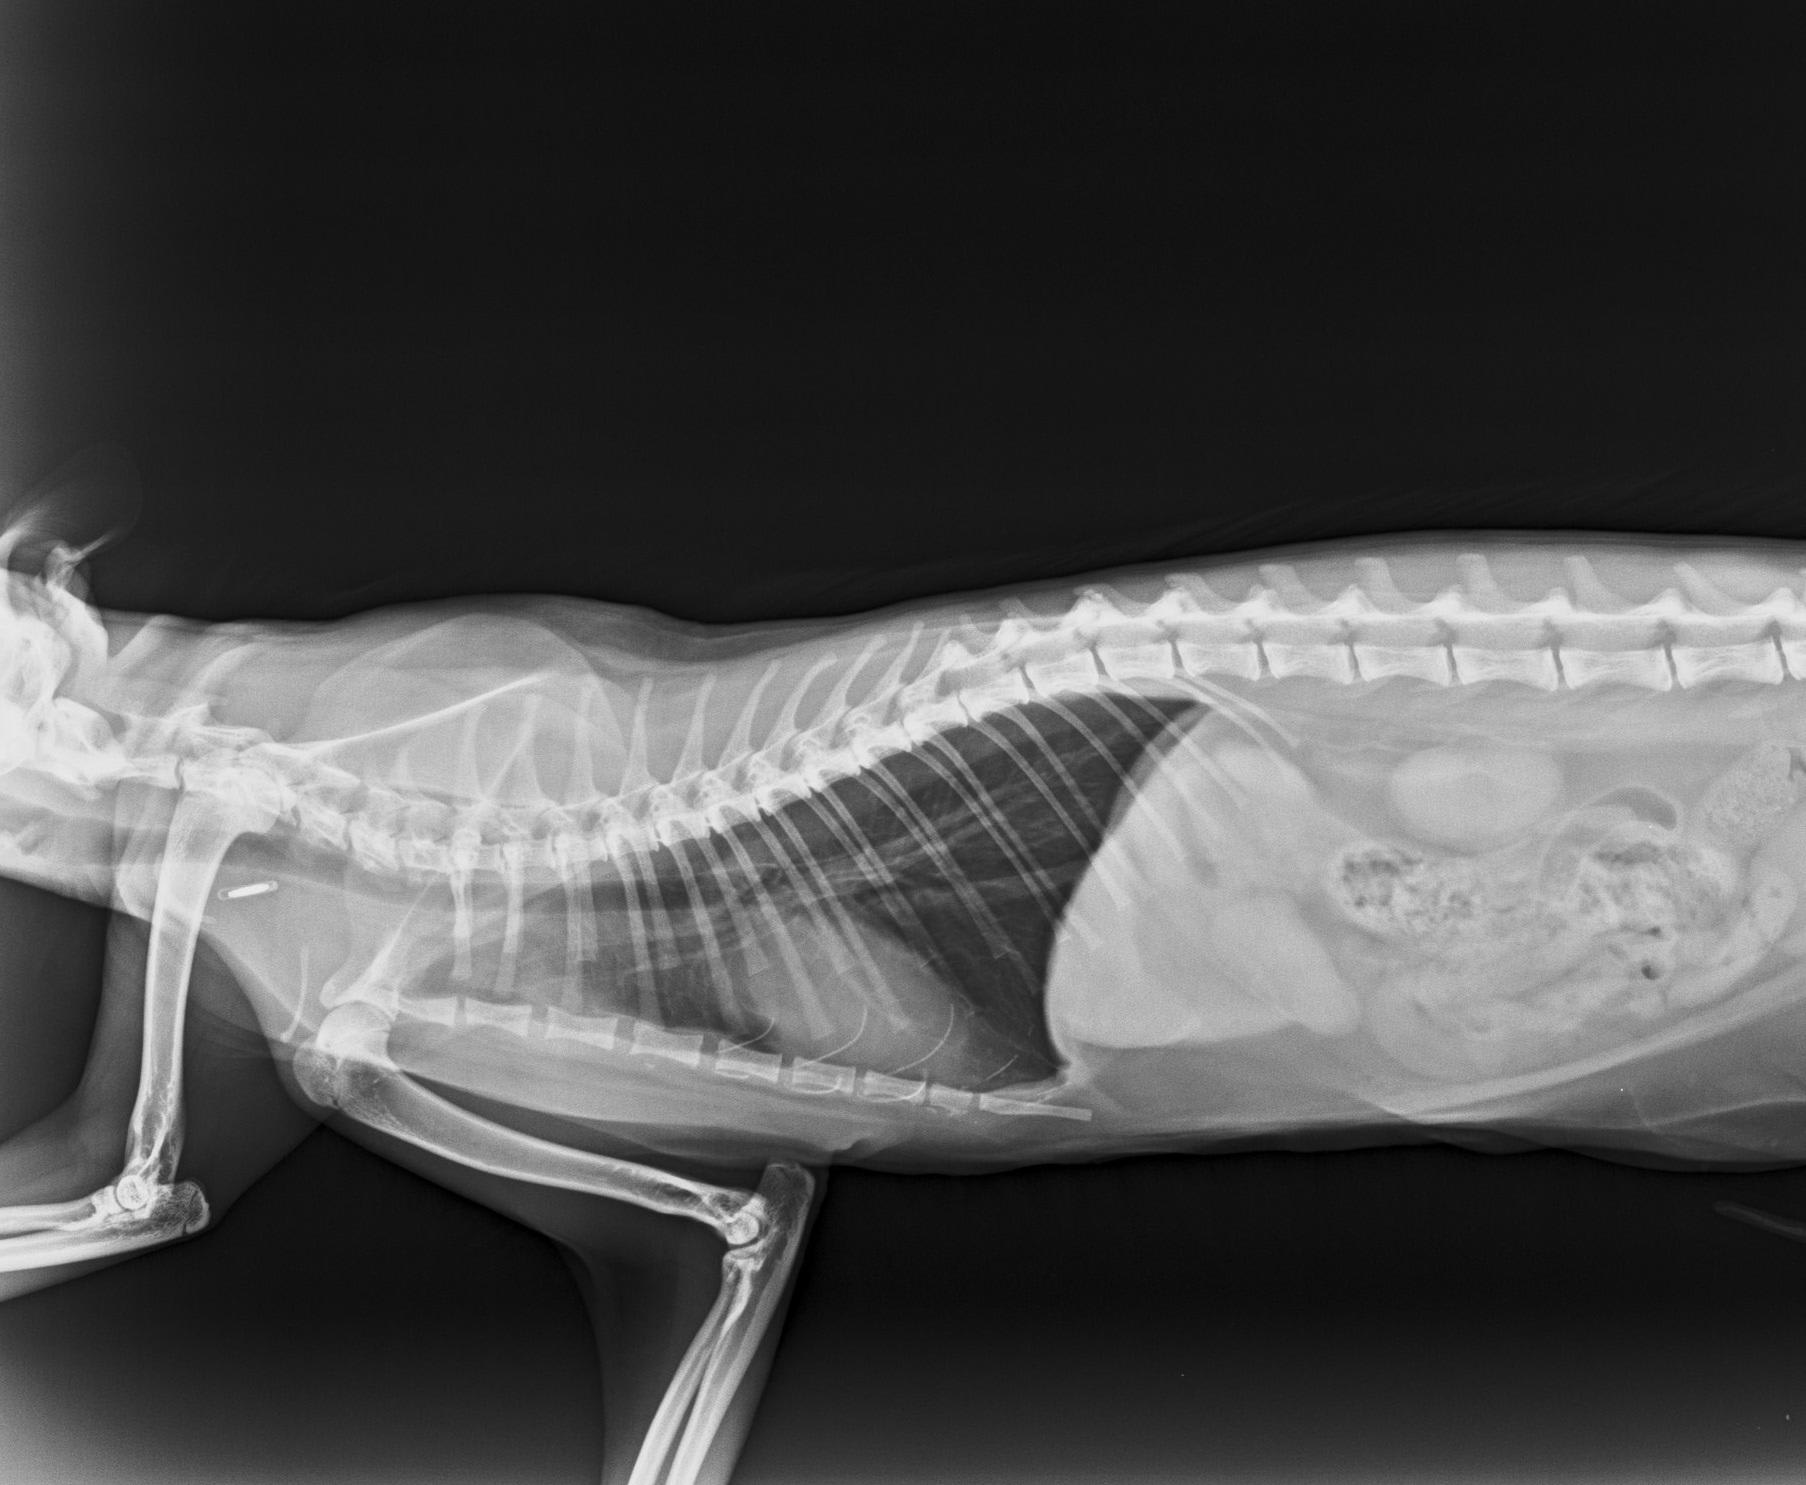

Hello, my cat (female, neutered, year and a half) had calicivirus. Now she limps and she can't jump to hight places. One vet says that she has osteoarthritis in the left elbow and right hip. He recommends growth factors and stem cells, not a surgical intervention.. The other veterinarian says that it is insufficient ossification because she is still too young. He recommends two weeks of calcium. These two oppinions are totally opposed. I don't know what to do. These are the x-rays. Thanks

You do not mention when she had the virus - this is commonly associated with severe lameness which resolves over time in most cases (there does also appear to be poor fusion or injury of one elbow). The xrays are very difficult to assess of the screen, especially as there are no markers to identify right from left limbs and the colour does not always reflect accuratley when transferred. They should not be diagnostic without comparing them to the full physical exam for muscle loss etc. A full review of her diet history would be worthwhile as poor kitten nutrition can lead to complications but generally it appears at an earlier age.